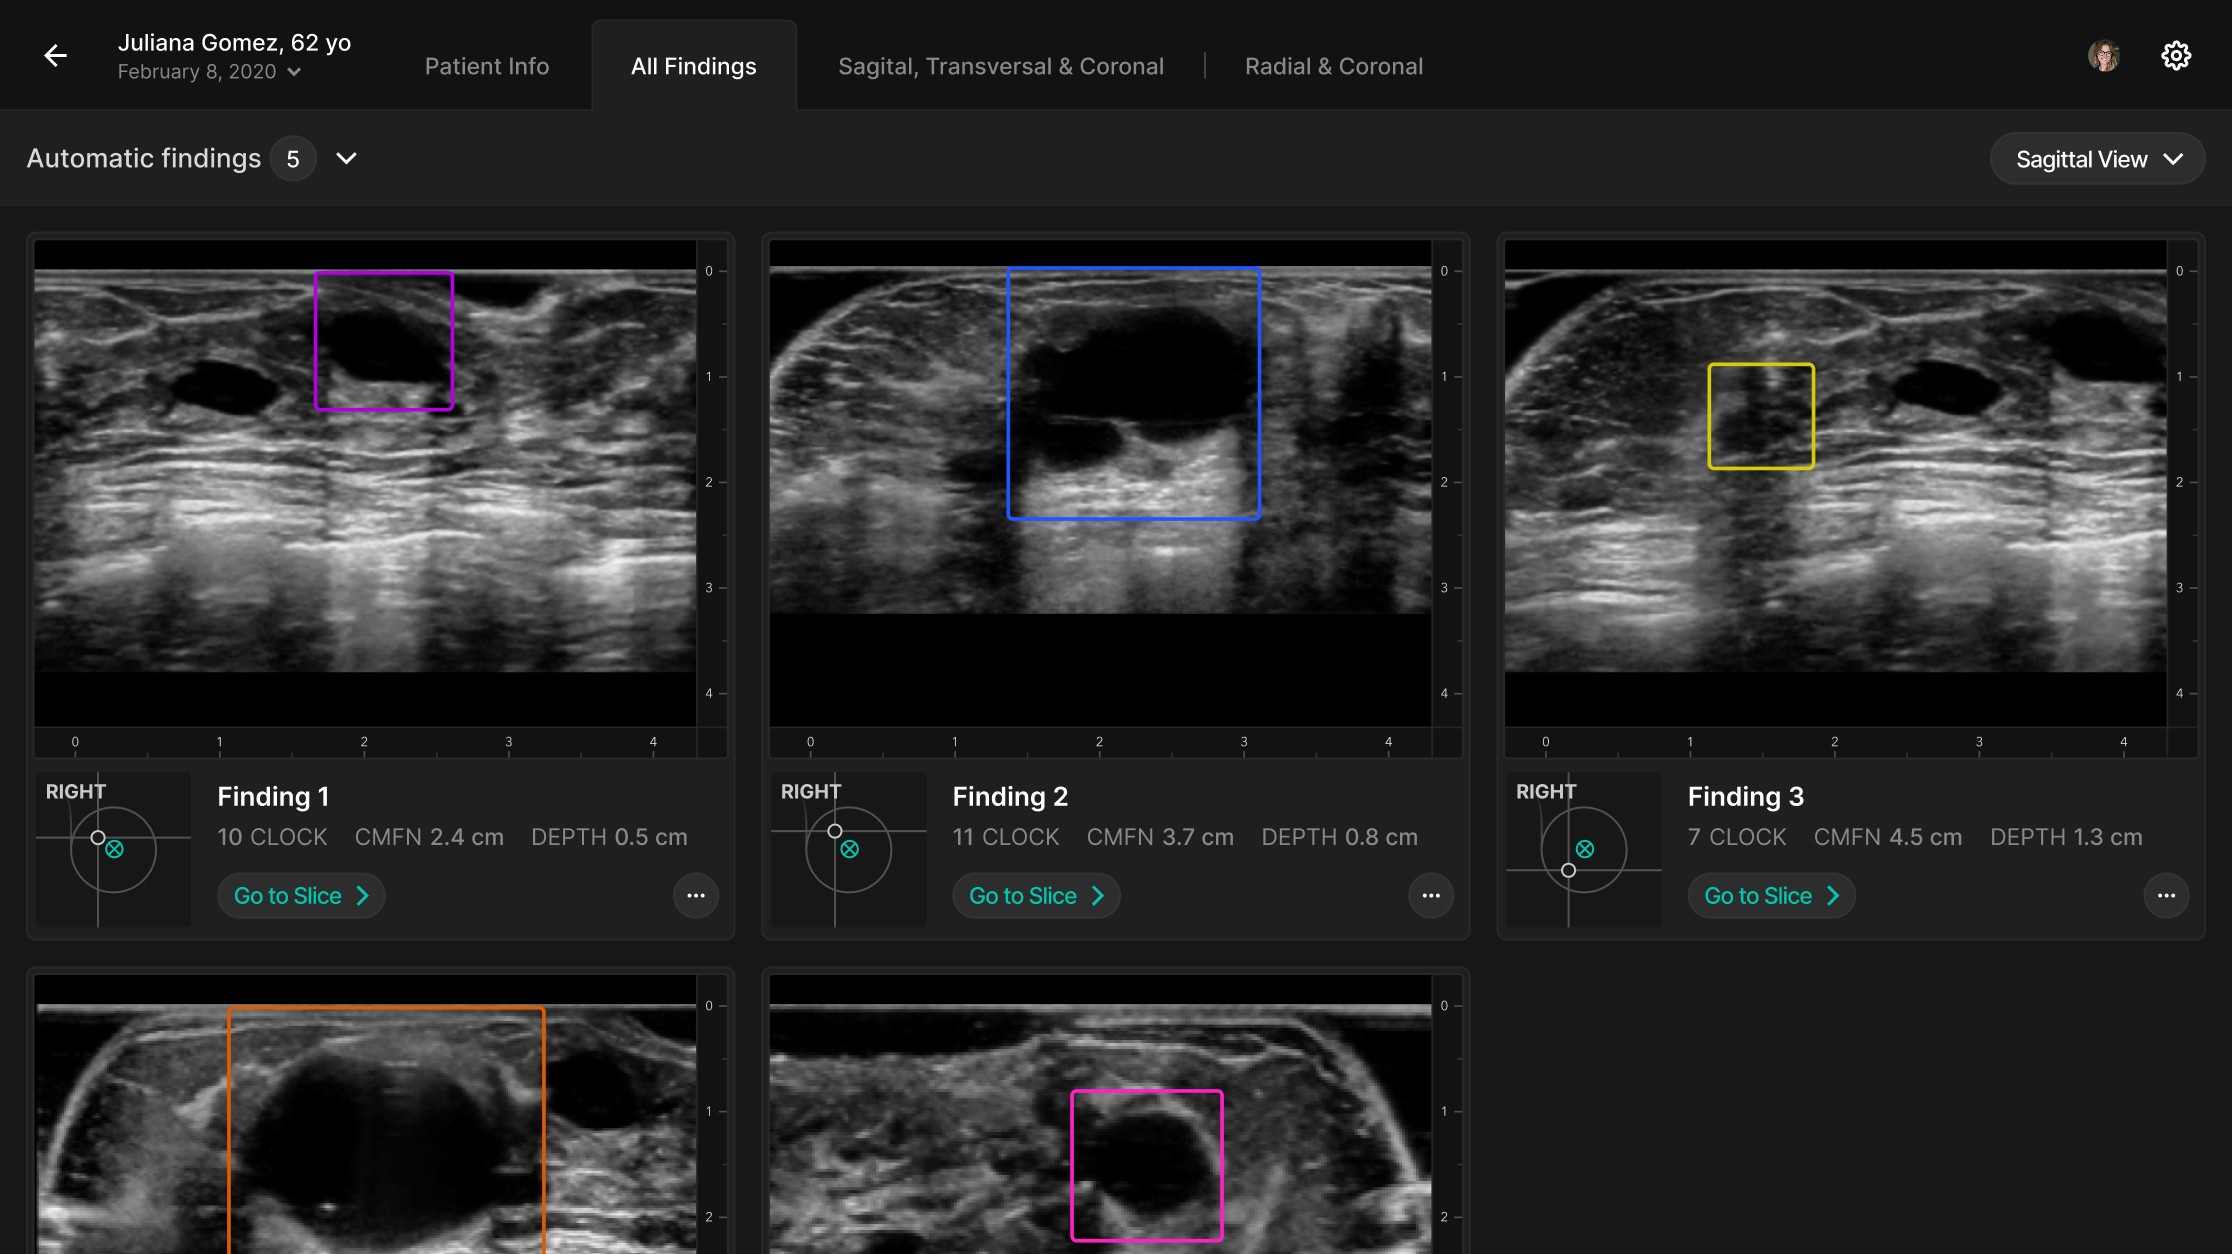

In UX/UI, we redesigned the review interface to surface only the most relevant 3D images (those flagged by AI), with an option to expand into a multi-plane comparison mode. The redesigned Scrubber allows radiologists to navigate slices quickly and correlate findings across planes, improving interpretation speed and clarity.

Refined the Radiologist Experience

Designed a new interface that surfaces AI-flagged 3D images first, reducing the number of slices to review and easing cognitive load.